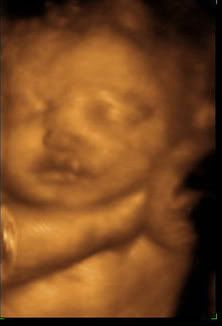

While looking at Amber's photos last night we compared AJ's ultrasound photos taken at 30 weeks and 5 days to Annabelle's ultrasound photo's taken at 30 weeks 2 days...

Initially, I thought AJ had big lips but looking back, it seems Annabelle did too!

Here are the two...

I'd say they look like sisters!! :)